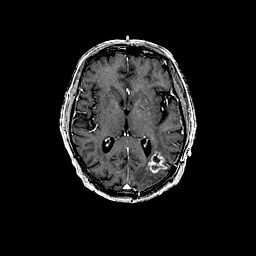

Glioma overlay -- Slice #59

[Home][Help][Clinical] Slice 59